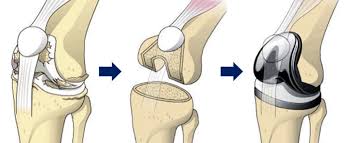

무릎 인공관절 수술, 왜 필요한가요?

무릎관절은 체중을 가장 많이 지탱하는 관절입니다. 나이가 들수록 연골은 점차 마모되고, 충격을 흡수하는 능력도 감소합니다. 이로 인해 통증, 뻣뻣함, 운동 제한이 생기며, 이런 증상이 악화되면 인공관절 수술이 필요해집니다.

퇴행성 관절염 외에도 류마티스 관절염이나 외상 후 관절 손상이 심각할 경우 수술이 권유되며, 수술을 통해 환자는 통증 없이 보행이 가능해지고 일상생활로 복귀할 수 있게 됩니다.